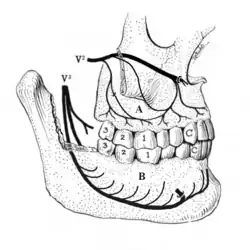

V2: maxillary division of trigeminal nerve, V3: mandibular division of trigeminal nerve, A: the superior alveolar nerves and plexus, B: the inferior alveolar nerve and plexus running in the body of the mandible.